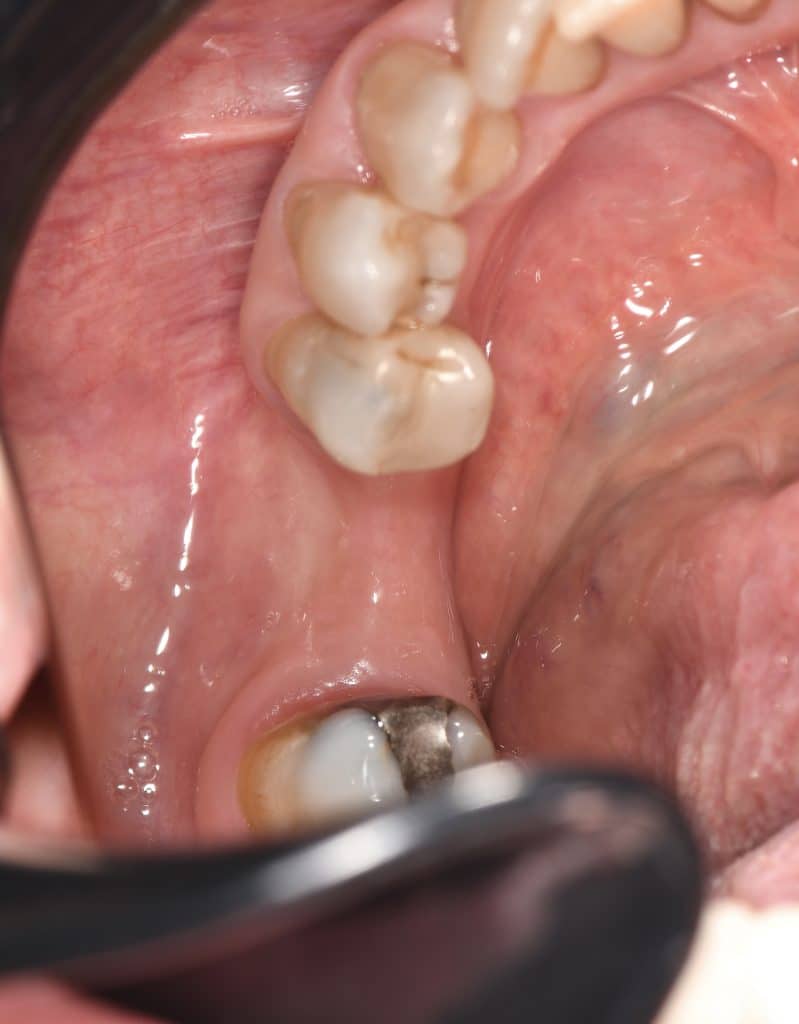

here a guided surgery case where a lower molar was replaces by an implant ,flapless ,thanks to a good digital planification and a realisation of a surgical guide